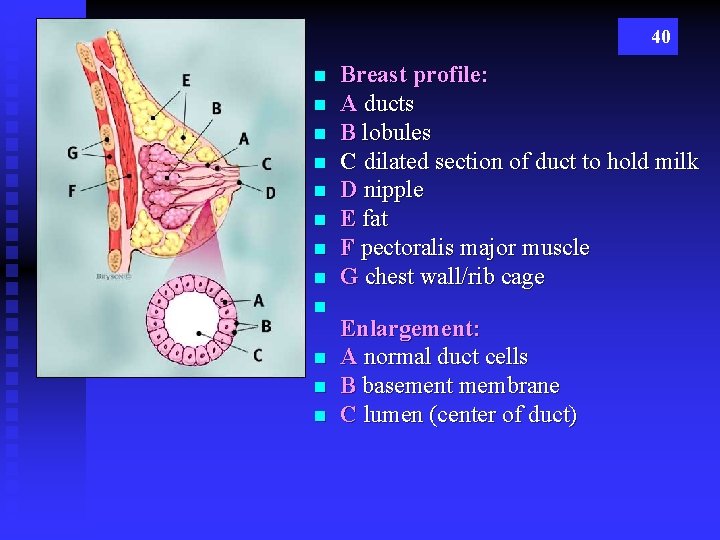

40 n n n Breast profile: A ducts B lobules C dilated section of duct to hold milk D nipple E fat F pectoralis major muscle G chest wall/rib cage Enlargement: A normal duct cells B basement membrane C lumen (center of duct)